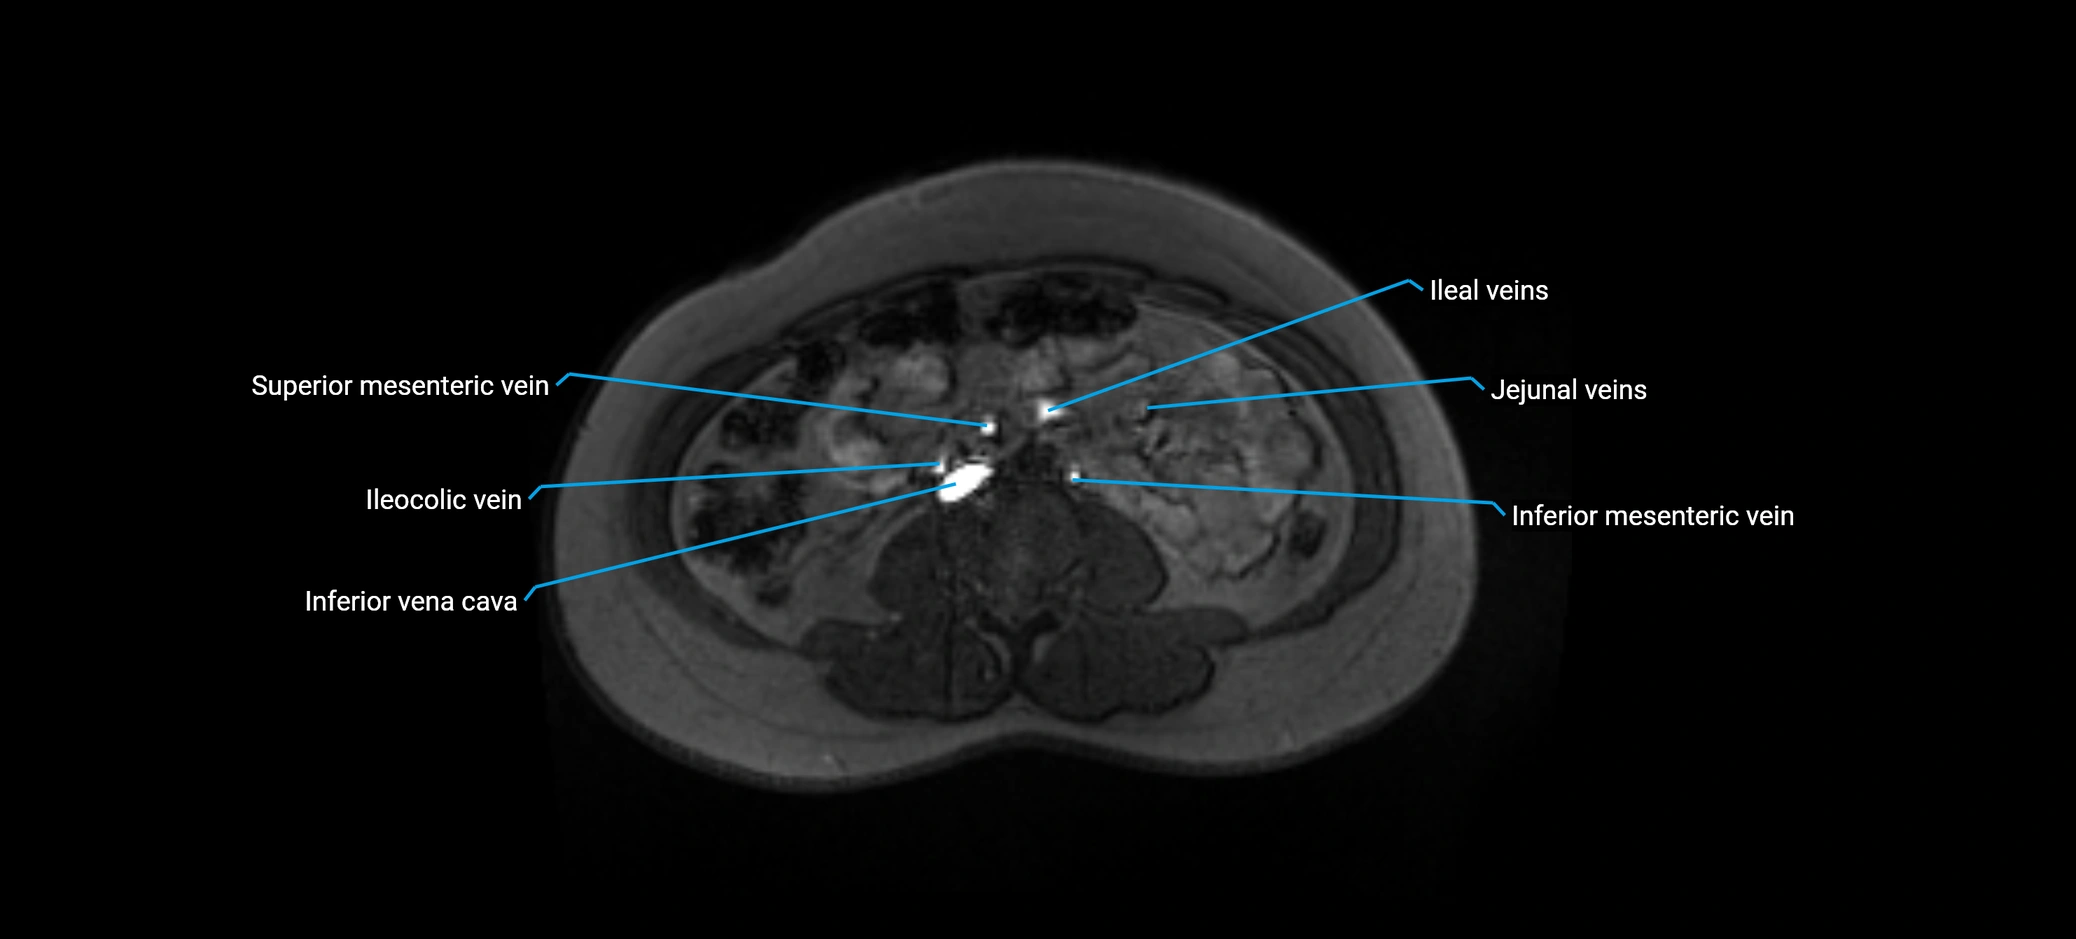

image